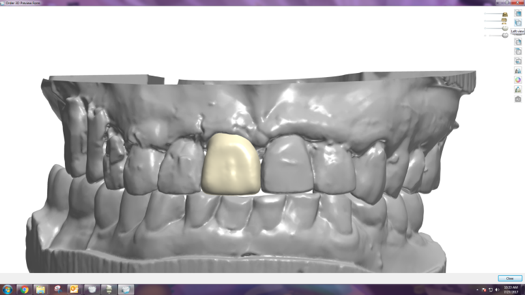

After completing an initial diagnostic appointment, a patient accepted three single-unit full-contour zirconia crowns that were milled from the digital impression and cut back for porcelain application. The application by a technician is analog dentistry. The ability of a dental laboratory to scan an analog crown-and-bridge impression is called converting an analog impression to a digital impression. The workflow after the conversion has become digitized. A dental model is virtually created with computer software, and a full crown proposal is fabricated for inspection virtually before the crown is milled (Figure 2). Due to the color of the digitized impression, the margins of the crown preparations are more easily and rapidly identified. The laboratory will also 3D print a working model, which will be used to develop the morphology of the final restoration by hand placement of porcelain (Figure 3). The decision to prescribe a full contour zirconia crown with cutback for porcelain application or complete full contour zirconia crowns lies solely on the attending dentist.9 A discussion with the patient before preparation of the teeth is imperative. After the discussion, the patient requested the zirconia copings with cutback and porcelain application for the posterior crowns (Figure 4 and Figure 5).

Fig 2. Digital impression and proposal of zirconia cutback before porcelain application.

Figure 2